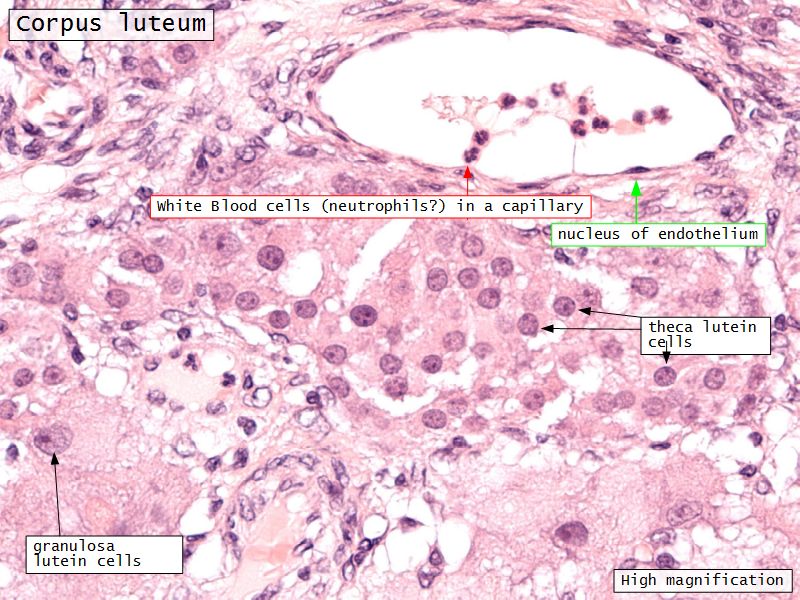

Corpus luteum

Slide 91

Corpus luteum

- Two major cell types

- Granulosa lutein cells

- modified granulosa cells

- Theca lutein cells

- modified theca interna cells

- Many capillaries

Granulosa lutein cells

- Modified granulosa cells

- Large - 30µm

- Pale cells

Theca lutein cells

- Modified theca interna cells

- Smaller - 15µm

- Dark stained